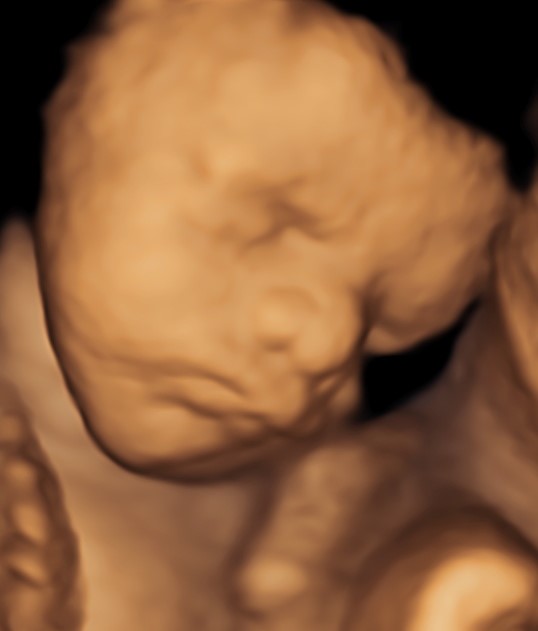

Monmouth County’s First 4D/5D/HD Live Ultrasound Studio

Gift certificates make a wonderful gift for mother’s to be. Monmouth counties first 3D/4D Ultrasound Studio is conveniently located just off Route 9 North, in Englishtown, NJ. Schedule your appointment today to create a memory of a lifetime.

4D/5D/HD Ultrasound Gallery